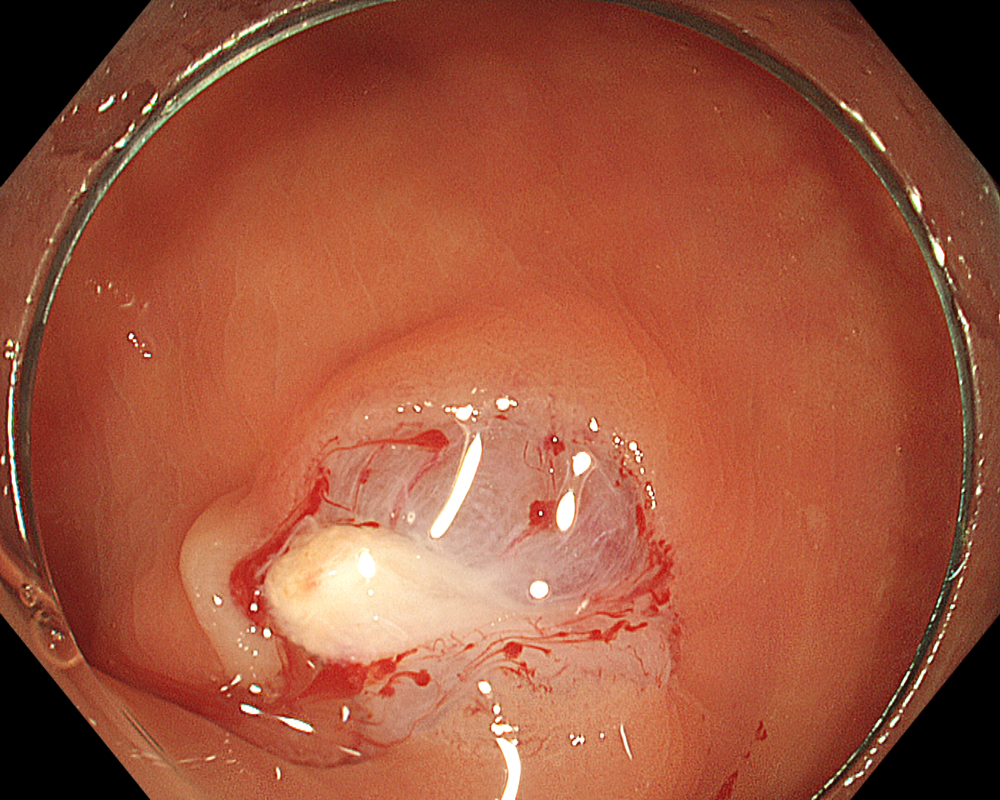

The points to note immediately after CSP are bleeding and residual tissue. Since CSP does not involve electrocautery, there is no so-called “burning effect.” Therefore, when capturing the lesion with the snare, it is important to include a margin of surrounding non-neoplastic mucosa. After CSP, re- examine the mucosal defect margin using NBI + Near focus to check for any residual tissue. Again, the EDOF function makes focusing and magnified observation significantly easier here.

While pulsatile or arterial bleeding is rare after CSP, minor oozing is almost always present. Applying the water jet to the post-CSP mucosal defect helps achieve a tamponade state for pressure-based hemostasis. Red Dichromatic Imaging (RDI) is a wavelength selection technology that enhances the visibility of deep vessels and bleeding points, making it useful for identifying bleeding sites and evaluating hemostasis. Even when a bleeding point is difficult to confirm, switching to RDI facilitates its identification, making hemostatic procedures and confirmation of successful hemostasis much easier and highly useful.